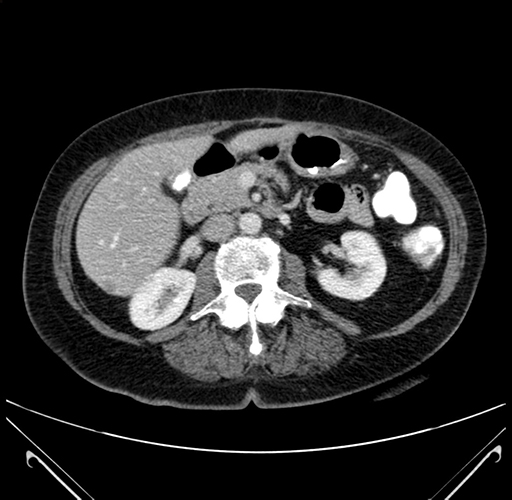

Pre-Chemo: Axial Venous

Axial Venous